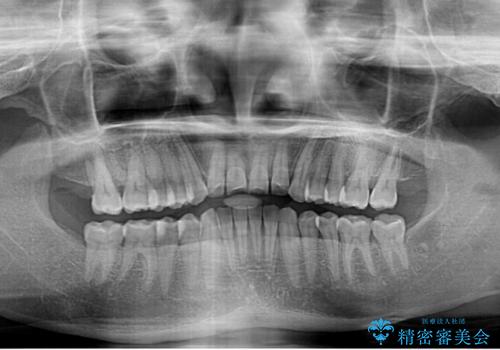

反対咬合の改善 途中で出産をしながらワイヤー矯正

- 前歯の隙間と反対咬合を気にして来院された患者様です。

マウスピース矯正も提案しましたが、しっかりと使用する自信がないとのことで、ワイヤー装置により矯正治療を行うこととしました。

咬合力が強く、反対咬合の改善に時間がかかりましたが、その後はスムーズに進めることができました。

途中、妊娠と出産があり、治療が中断したため、治療期間は延びましたが、出産も矯正治療も無事に終えることができました。